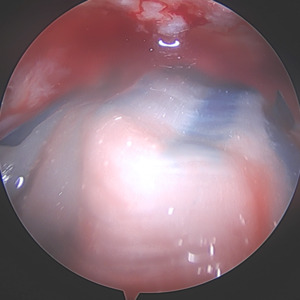

This 48-year-old male is a right hand dominant, nonsmoker with an active lifestyle. This patient presented with excellent range of motion and passing inactive range. Upon examination, strength presented at 5/5 rotator cuff, mild tenderness over the proximal long head of the biceps, but positive for subacromial impingement testing. Imaging revealed a skeletally mature individual with an intact glenohumeral joint space without signs of osteoarthritis and an intact acromial-humeral height distance (Figures 1-3).

The MRI revealed an anterior full-thickness supraspinatus tear from the origin with mild retraction and moderate delamination. Fluid signal was seen within the mid-substance of the supraspinatus tendon medial to the location of full thickness tear. Subchondral cystic changes in the greater tuberosity were also observed at the insertion site. (Figures 4 & 5)

Due to the delaminated nature of the tear and active work as a laborer, biologic augmentation (TAPESTRY® Biointegrative Implant by Embody) was added to support tendon healing. This biologic augmentation was chosen due to the delamination and retraction of the rotator cuff as an increased change of retear is noted when present. The arthroscopic introducer was used from the lateral portal via the cannula. Once appropriately positioned over the delaminated area, three bioabsorbable anchors were used to fixate the implant in the tendon and bone, with two anchors placed medially in the soft tissue and two anchors placed laterally into bone.

I chose to include biologic augmentation due to the extensive delamination seen on the preoperative MRI as well as intraoperative findings. Several preoperative patient risk factors (age, BMI, smoking, diabetes) may be reviewed when considering biologic augmentation of a tear due to increased risk of retearing or poor healing. The bioaugmentation used is a highly aligned, porous collagen implant which supports formation of new tendon-like tissue. The alignment and significant porosity of the implant allows for increased cell proliferation and remodeling. The implant covers a wide surface area and can be precisely placed arthroscopically over the area of concern. Another benefit of the bioaugmentation implant is that it may increase tendon thickness during healing, which could allow for better post-operative results. Furthermore, using it to augment the tendon does not require any additional post-operative protocols outside of the standard protocol.